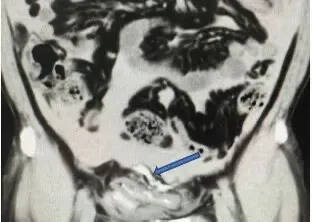

急诊团队马上为张先生执行导尿并进行腹部CT查验,同期关连泌尿外科团队进行病例运筹帷幄。影像后果知道,本应存在于膀胱内的造影剂竟出现于腹腔中,纠合患者腹部受击打、无数饮酒后永劫刻憋尿的病史,确诊为膀胱离散。

箭头处可见外渗进腹腔的造影剂